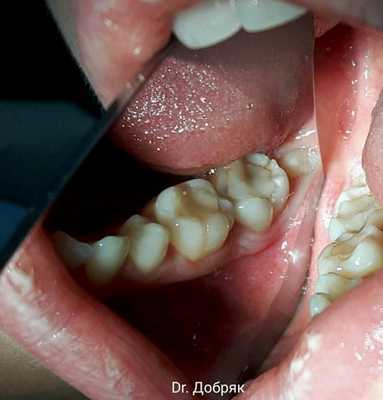

1 год и 8 месяцев назад обратилась пациентка в клинику с жалобой на подвижность стенки зуба 47. После проведённого осмотра и КТ, выявлено две трещины - вертикальная до бифуркации и медиальная часть зуба по бугру. Также обратил внимание на наличие 48 зуба и схожесть формы корней. Пациентке было предложено провести пересадку (реплантацию) зуба 48 на место 47, все страхи и риски были оговорены, мы решили пробовать.

После реплантации зуба швы были сняты на 2-ой недели. Зуб находился вне окклюзии.

Далее осмотр через 3 недели и 3 месяца, на 3-м месяце подвижность зуба отсутствует.

Спустя 5,5 месяцев зуб депульпирован и покрыт коронкой (Cerec, E.max).